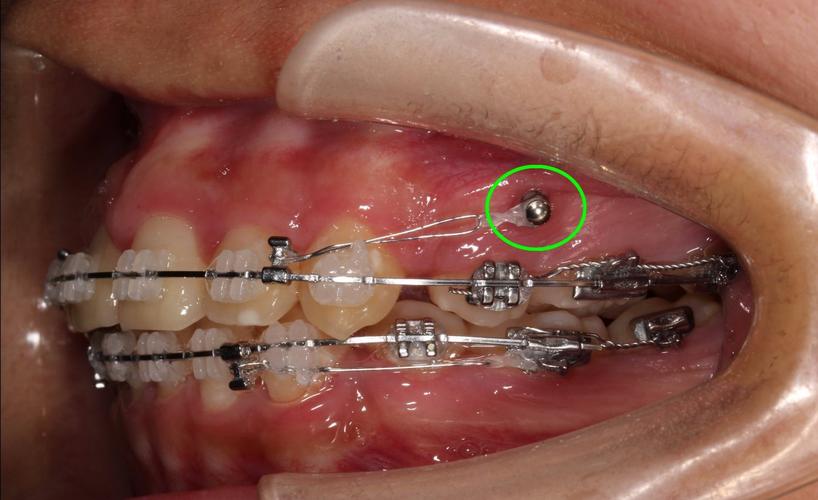

视频的重点环节往往集中在种植钉的植入流程,这部分内容常结合动画演示与实拍画面,清晰呈现每一步操作,术前准备阶段,医生会强调影像学检查(如CBCT)的重要性,以避开牙根、神经血管等解剖结构,确定安全植入位置;同时进行口腔清洁(如洗牙、刮治),确保植入区域无炎症,局部麻醉是关键步骤,视频会展示麻醉药物注射过程,说明麻醉后区域仅感压迫感而无痛感,植入操作中,医生先用微创切口器在牙龈上做小切口(约2-3mm),随后用专用手机备洞(在牙槽骨上制备适合种植钉的窝洞),再将种植旋入窝洞,最后调整露出牙龈部分的高度(约1-2mm,便于后续正畸加力),整个过程通常5-10分钟,创伤小、恢复快。

为帮助患者更直观理解,视频常通过表格对比不同类型种植钉的特点,按植入部位可分为上颌种植钉(如颧骨、腭部、牙槽间隔)和下颌种植钉(如下颌后牙区、颏部),上颌骨骨质较疏松,植入时需注意角度避开上颌窦;下颌骨骨质致密,备洞时可能需要更大扭矩,按材质可分为钛合金种植钉(生物相容性好、强度高,临床应用最广)和不锈钢种植钉(价格较低,但部分患者可能对金属过敏),表格还会列出适用场景,如钛合金种植钉适用于需长期稳定支抗的病例,而不锈钢种植钉多用于短期、简单的牙齿移动控制。